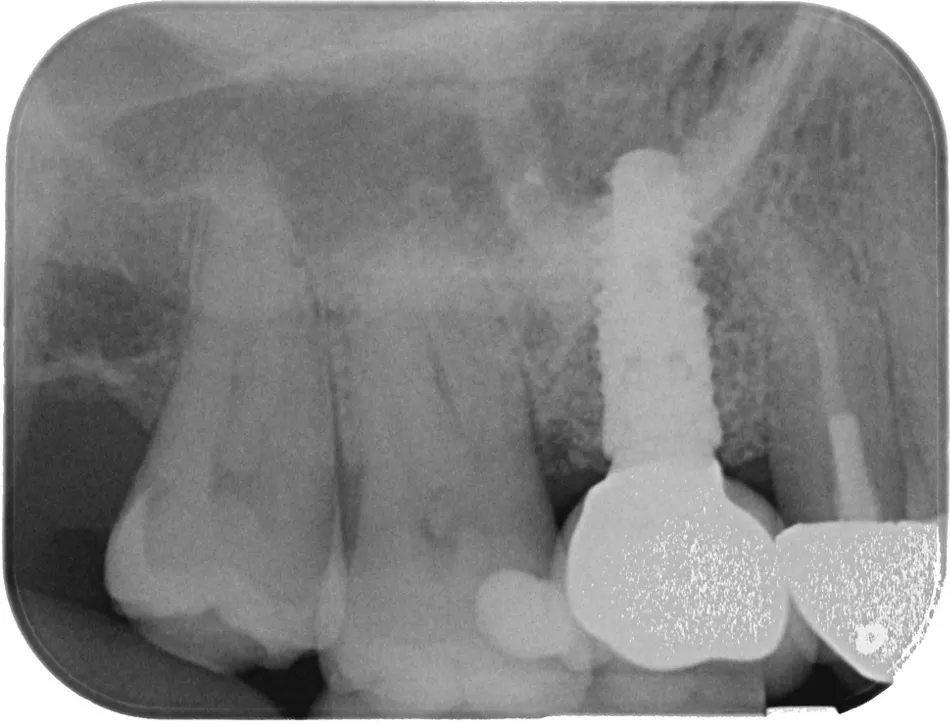

The intraoral examination showed localized inflammation around the implant in region #16, characterized by redness, swelling, bleeding on probing, and the presence of suppuration. The radiographic evaluation revealed vertical bone loss adjacent to the implant, while horizontal bone availability and bone quality remained within acceptable limits. The prognosis of the remaining dentition was favorable based on the clinical and radiographic findings (Fig. 1).

Fig. 1

Comprehensive clinical and radiographic findings led to the diagnosis of peri-implantitis at region #16.